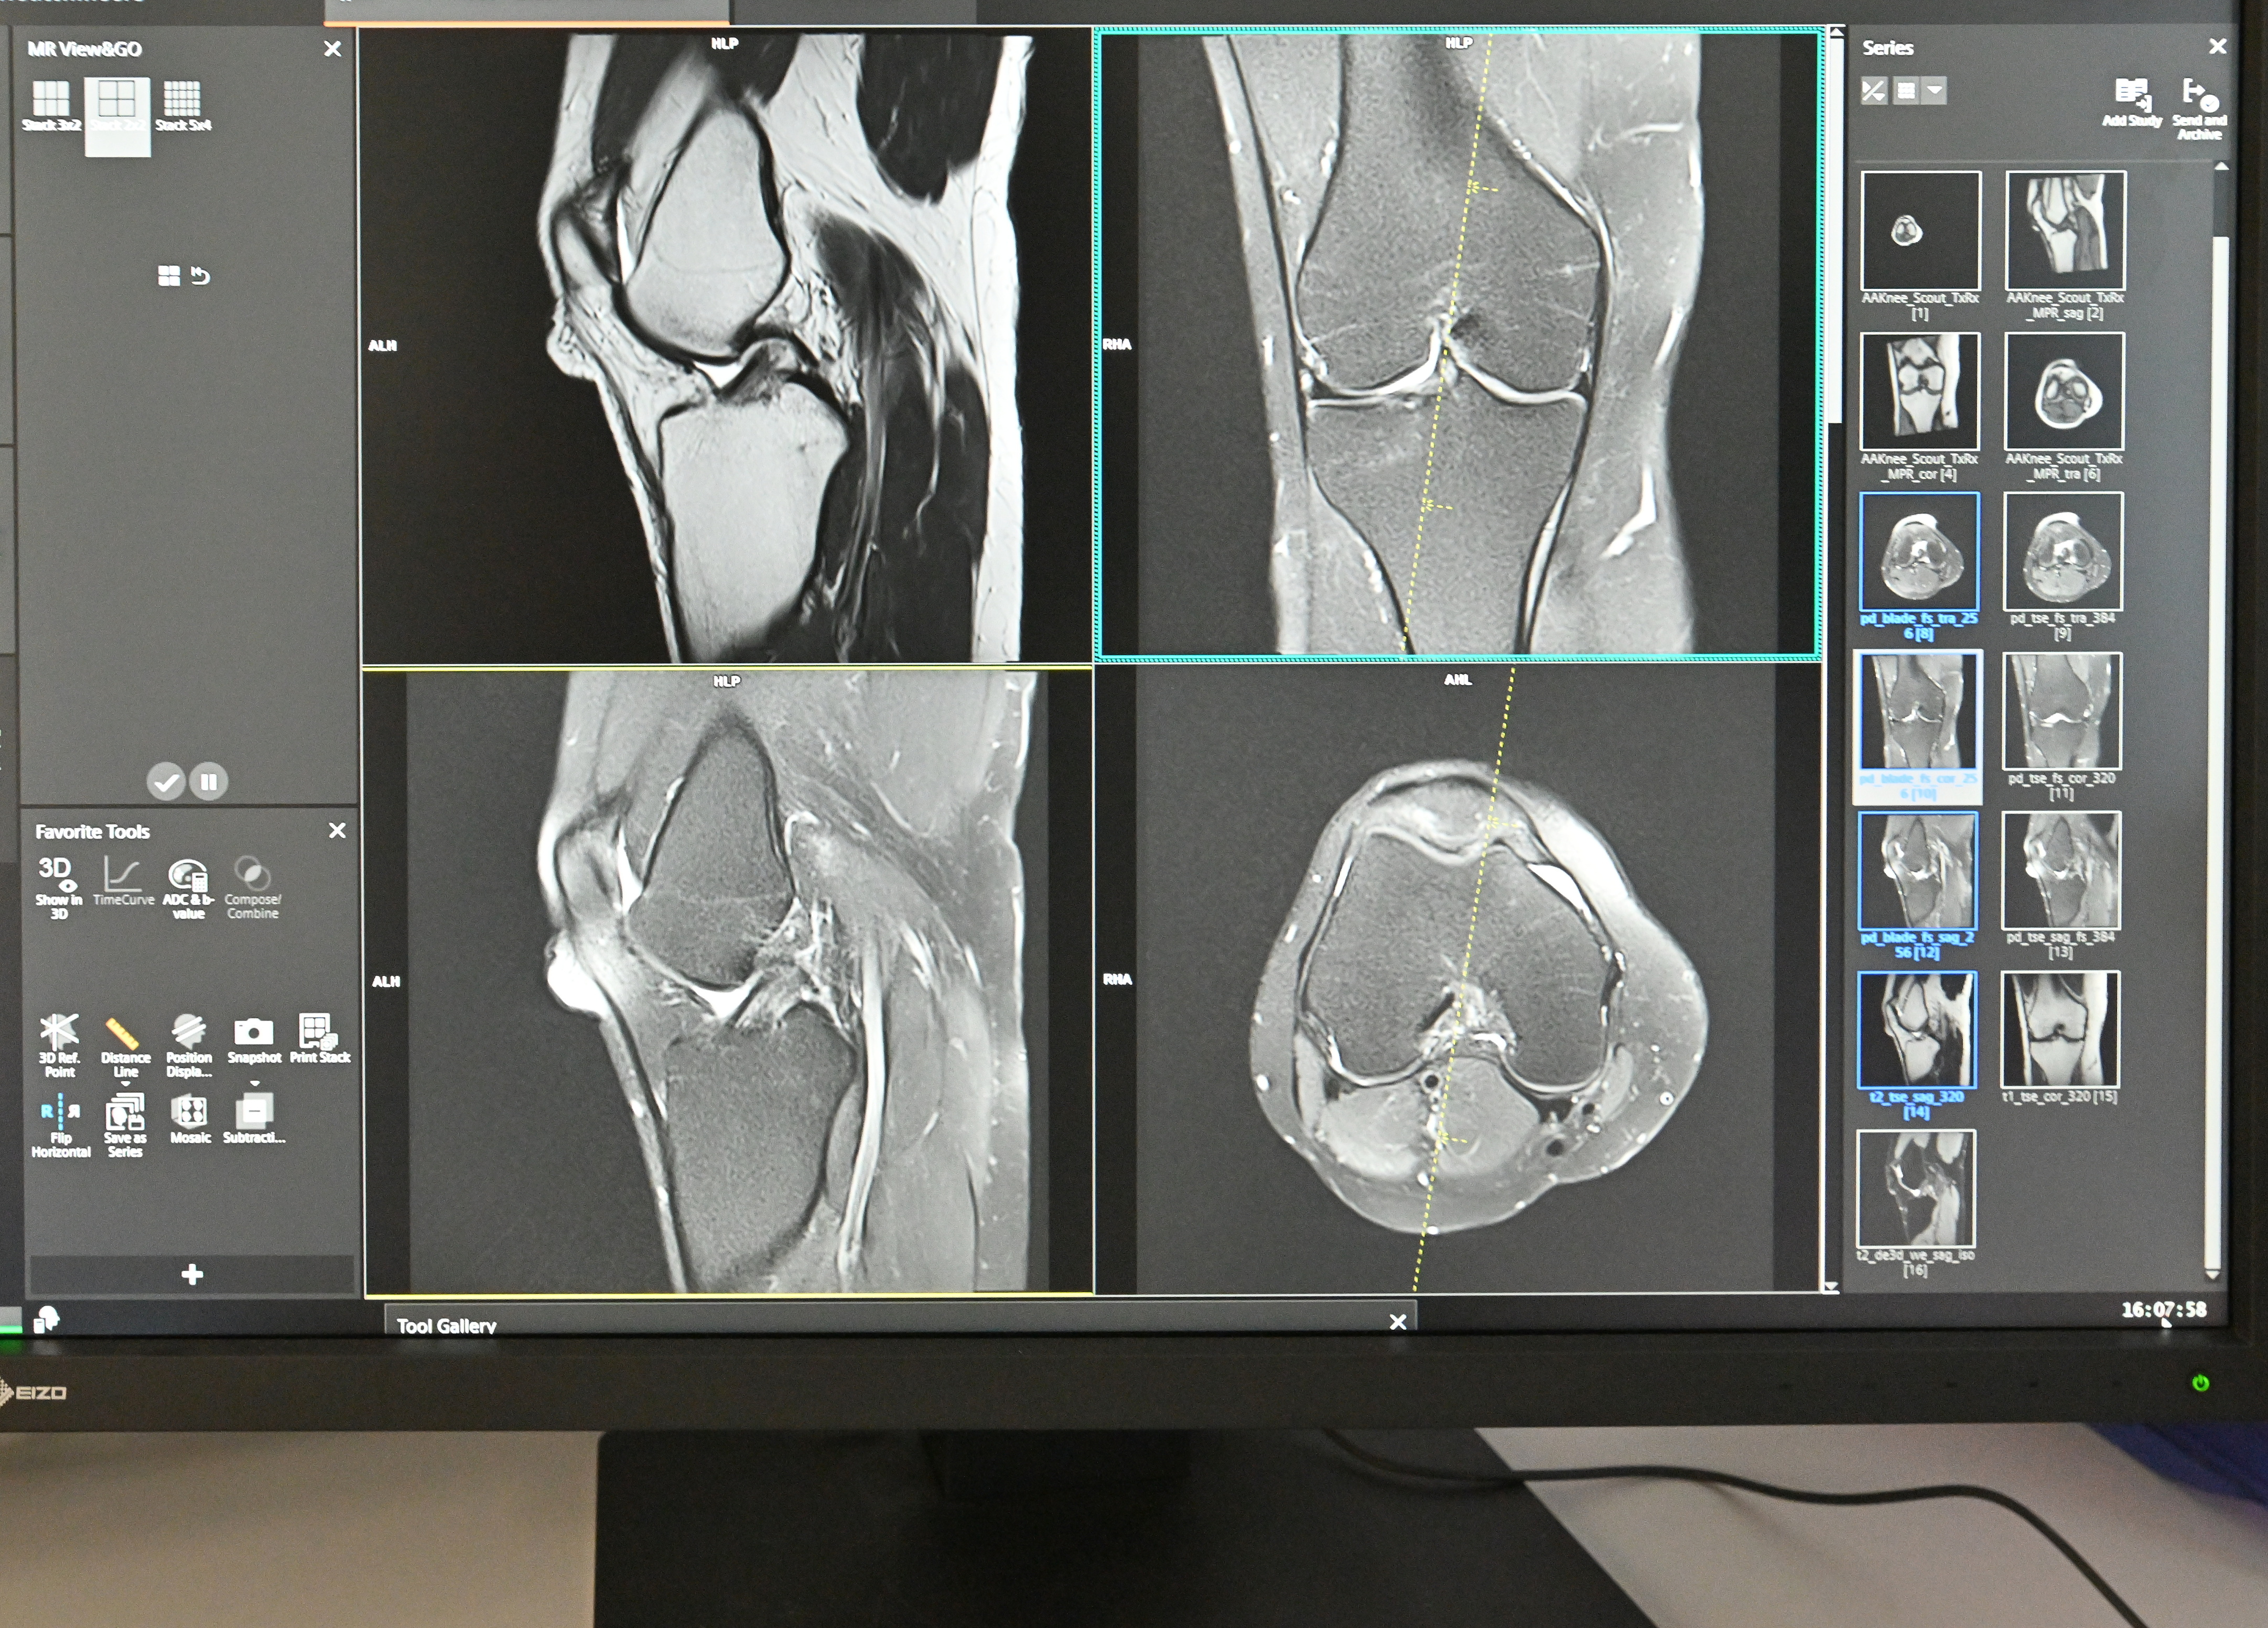

Lidé z Liberce a okolí se na magnetickou rezonanci dostanou průměrně do deseti dnů. Zatímco v jiných částech republiky čekají mnohdy týdny až měsíce, v EUC Klinice Liberec mají jistotu, že se na toto důležité vyšetření dostanou včas. Klinika pro velký zájem pacientů rozšiřuje od ledna odpolední ordinační hodiny, nově nabídne i sobotní termíny a plánuje vyšetřit až o 150 pacientů měsíčně více.

Pracoviště magnetické rezonance funguje v EUC Klinice Liberec od loňského podzimu. Zatímco před jeho otevřením čekali liberečtí pacienti na vyšetření až 6 týdnů, po něm se čekací doba zkrátila na dva až tři týdny. „Od ledna bude objednací lhůta ještě kratší. Vyšetření budou nově probíhat i v sobotu, a to od 8 do 17 hodin. Zároveň prodlužujeme odpolední ordinační hodiny. Aktuální pracovní doba byla od 7 do 13 hodin, nyní budeme v pondělí a úterý vyšetřovat do 16 hodin a ve středu a čtvrtek až do 18 hodin,“ uvedl Mgr. Radim Zika, ředitel EUC Kliniky Liberec.

Za první rok existence vyšetřilo pracoviště více než 3 000 pacientů. Průměrný věk pacientů byl kolem 50 let a ve většině případů šlo o vyšetření pohybového aparátu, páteře nebo mozku. „Naším cílem je vyšetřit měsíčně o 130 až 150 pacientů více než doposud. Zájem je velký,“ dodává Mgr. Radim Zika.